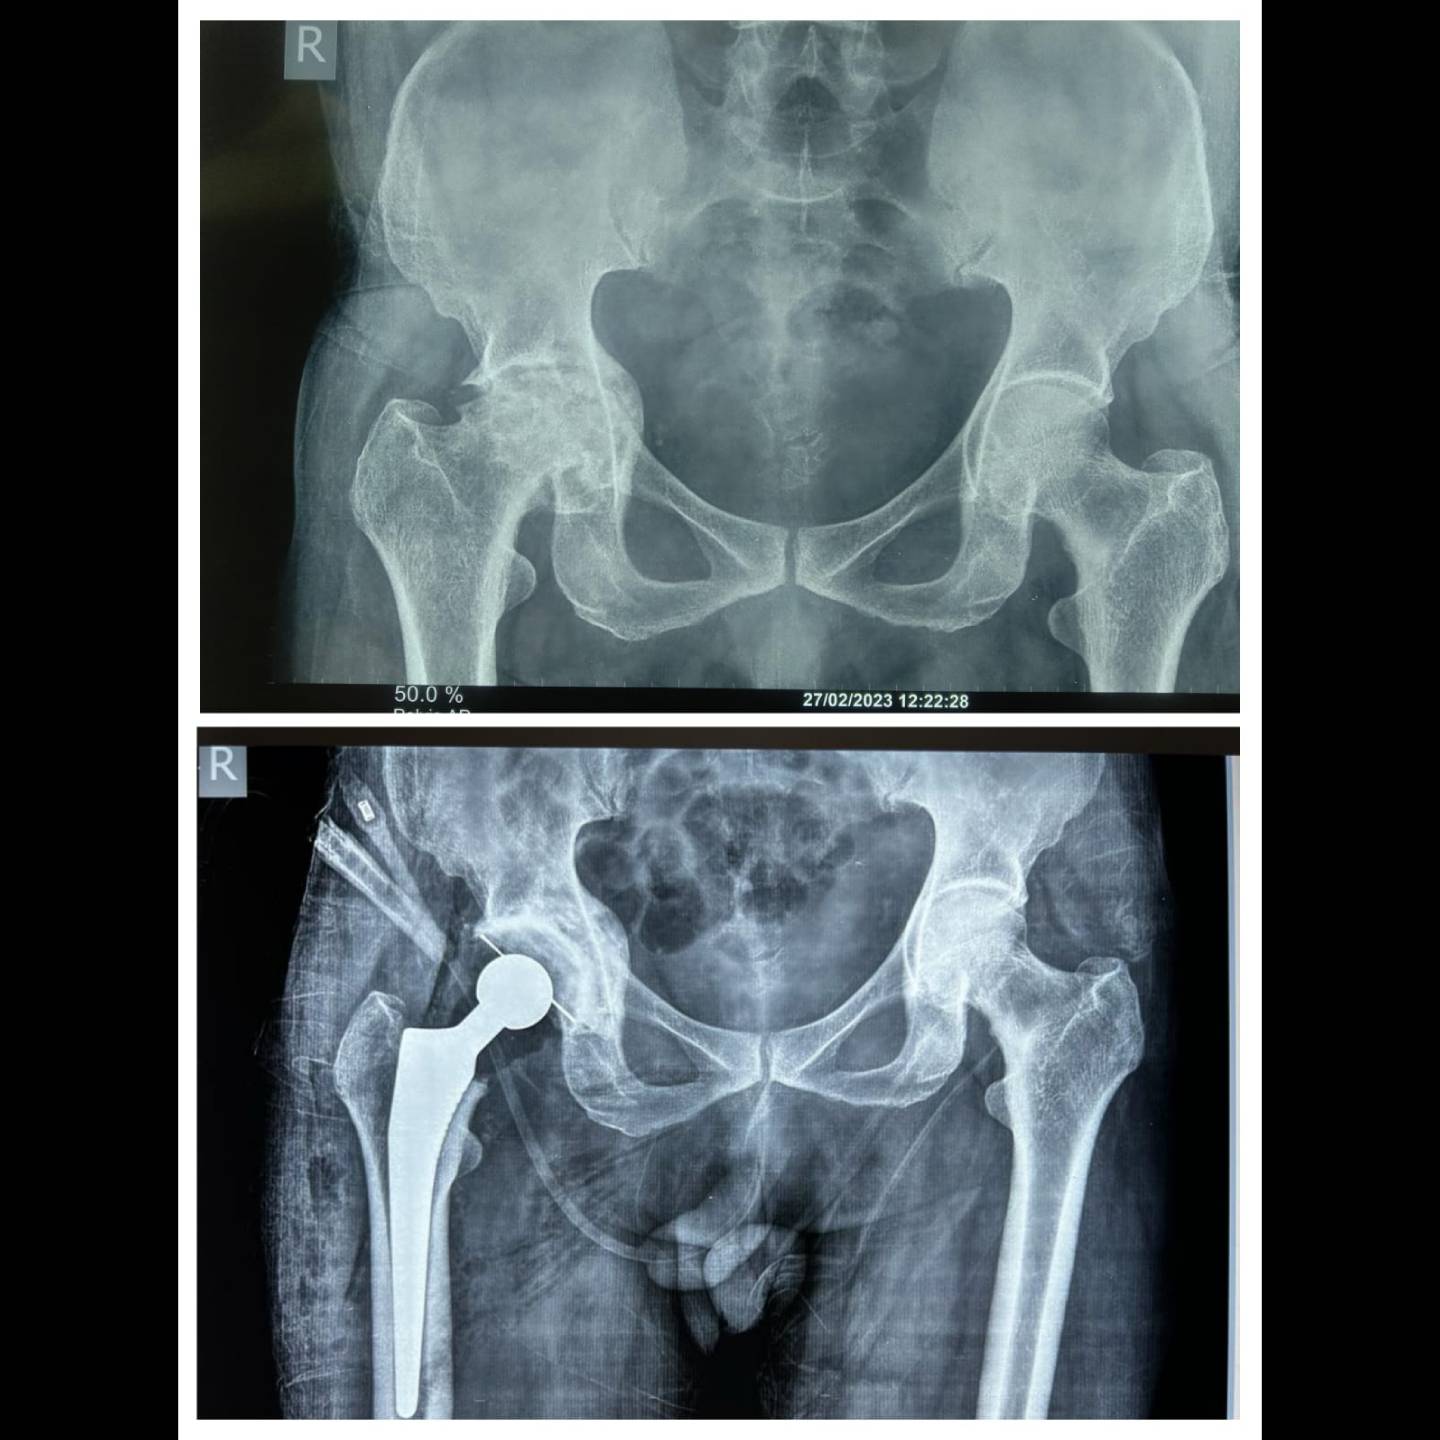

complex total hip replacement done in a 67 y old gentleman with severely degenerated hip.